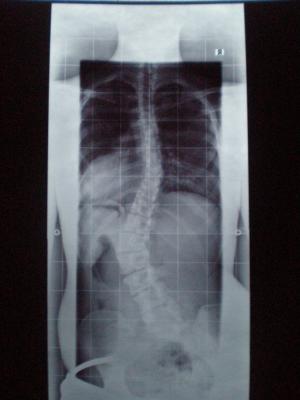

gestern hatte ich mein Röntgen im Korsett..

th. von 36° auf 19° im Korsett + Erhöhung 1.5 cm und

lu. von 50° auf 15° im Korsett + Erhöhung 1.5 cm :)

hätte ich nicht gedacht das man das noch von 50 auf 15 grad schafft ..

ich hatte eher damit gerechnet das die Grade im thorakalen Bereich weniger werden..aber naja..so ist auch gut :)

Ich hab die Röntgenbilder abfotografiert..

werd sie auch mal mitreinstellen..

th. 19° lu. 15° mit Korsett und mit Erhöhung 1.5 cm

th. 36°  lu. 50° ohne Korsett und ohne Erhöhung